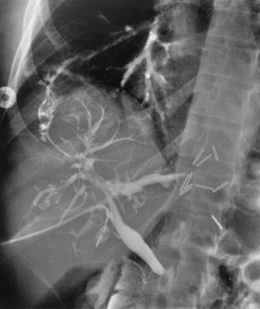

Hình 1: Hình ảnh khối u gan sau can thiệp nút mạch hóa chất (TACE)

Hình 5: Hình ảnh rò phế quản mật trên chụp đường mật xuyên gan qua da

Xử trí, đầu tiên cần phải giải áp đường mật để giảm áp lực chênh lệch trong ống mật chủ và tá tràng. Nếu giải áp đường mật không thành công và lỗ rò vẫn còn trên chụp đường mật, có thể cân nhắc tắc mạch qua da hoặc nội phế quản của đường rò. Phẫu thuật được chỉ định khi bệnh nhân không đáp ứng với phương pháp điều trị xâm lấn tối thiểu